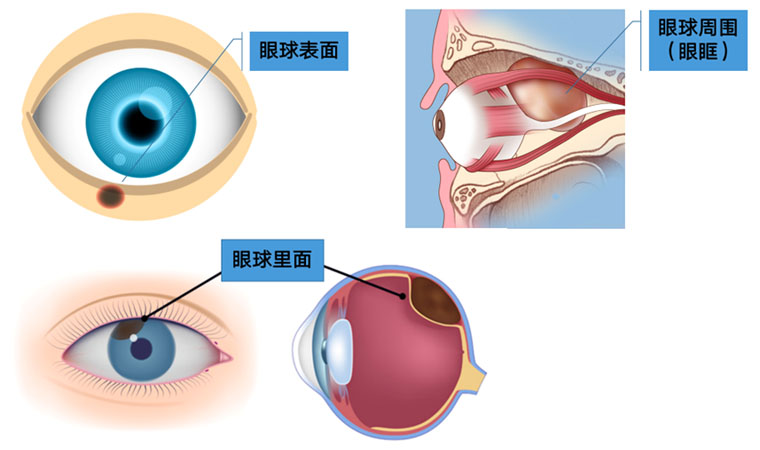

毫无疑问,无论是眼睛表面还是眼睛里面甚至是眼睛周围,都可能长肿瘤;而且眼部肿瘤也会发生在各个年龄段,包括婴儿、青少年、中老年都有可能发生眼部肿瘤。但是肿瘤也分良性和恶性,大多数人即使长了肿瘤很有可能是良性的,有一少部分人会得眼部恶性肿瘤。

眼肿瘤包括眼睑、结膜、眼内、泪器、眼眶肿瘤。眼睑恶性肿瘤常见基底细胞癌,睑板腺癌、鳞状细胞癌和黑色素瘤,良性肿瘤常见于色素痣和血管瘤;眼眶肿瘤包括淋巴瘤、腺样囊性癌、海绵状血管瘤、神经鞘瘤、神经纤维瘤等;眼内肿瘤以恶性多见,主要见于视网膜母细胞瘤、脉络膜黑色素瘤、脉络膜转移癌等。

眼睛表面的肿瘤很容易被发现,眼球后边(也就是眼眶)和眼睛里面的肿瘤常被人忽视或延误治疗,这些隐藏起来的肿瘤会影响眼球的位置,导致眼睛斜视或者眼球慢慢突出。眼睛里面的肿瘤最不容易发现,小孩子有可能表现为瞳孔发白,大人则往往到影响视力了才被发现。